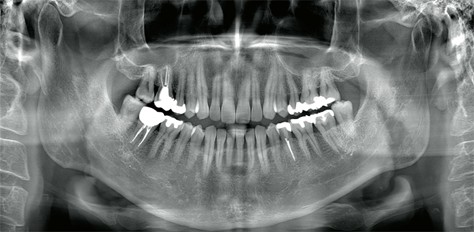

歯列全体を一目で確認できる『パノラマX線撮影』

お口全体の健康チェックを

パノラマX線撮影は、上下の歯列・顎の骨・顎関節を一度に撮影できる検査です。お口全体の健康状態を把握し、異常を早期発見するのに役立ちます。

こんな診断に活用されます

- 虫歯・歯周病の進行確認

- 歯根や骨の状態チェック(根尖病変・骨吸収の有無など)

- 親知らずの位置や生え方の診断

- 顎関節や顎の骨の異常発見

- 初診時の総合診断・定期検診での経過観察

目に見えない病変を早期発見できるため、症状が出る前の予防ケアにもつながります。

お口の状態は日々変化するため、年1回のパノラマX線撮影を推奨しています。